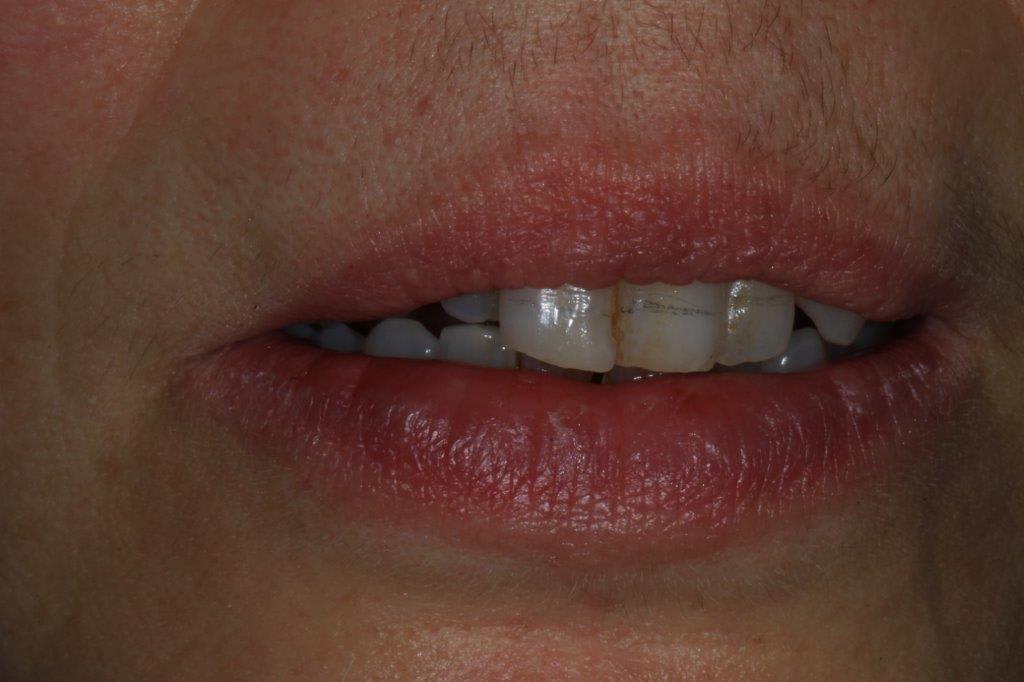

un peu de grain à moudre, toutes les critiques sont les bienvenues...

1ere séance,"nettoyage...", et après réflexion, plutôt que le nettoyage par le vide, attelle de contention pour le bloc antérieur mandibulaire, suppression de quelques contact très parasite sur les pm et canines, et réduction des incisives mandibulaire puis maxillaire... consignes de brossages / bain de bouche avec .... l'érythritol afin de ne pas mourir idiot... on verra ce que ça donne dans un cas relativement perdu d'avance.... merci Algi... enfin peut être : -))

C est dommage que l'on ne voit pas les dents en occlusion .

La 12 est en occlusion inverse et le secteur postérieur 20/30 aussi ?